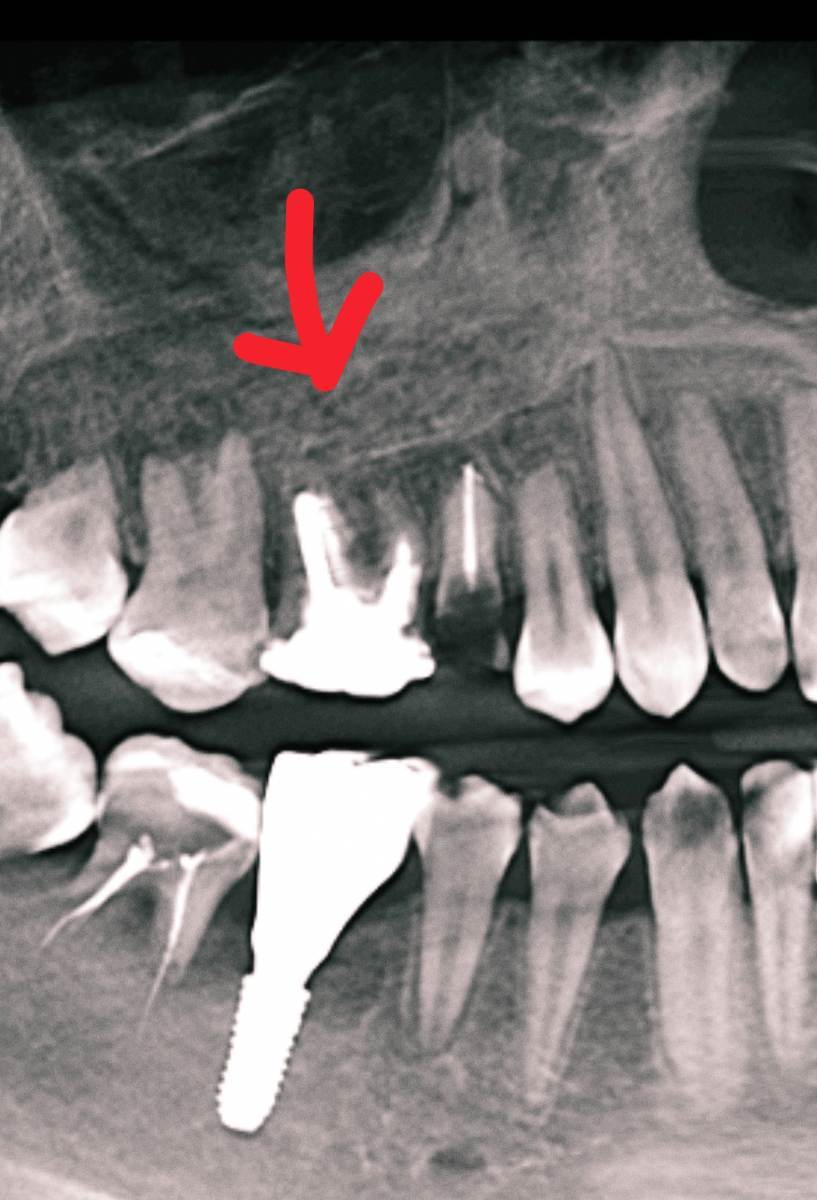

Добрый день, пожалуйста объясните что с зубом простыми словами, я если честно ничего не понял, там проблемы? Просто к стоматологу пойду через неделю только чтобы мне объяснили КТ, хочется сейчас узнать хоть что-то:

16 зуб эндодонтически лечен. Коронковая часть восстановлена рентгеноконтрастным материалом.

Небный корень: канал широкий, обтурирован высококонтрастным материалом, верхушка корня не закрыта. Периапикально очаг деструкции костной ткани 4,5х4мм. запломбирован.

Щёчно-медиальный корень – признаки дилацерации корня, канал запломбирован частично. Периапикально очаг деструкции 4х4мм

Щёчно-дистальный корень: длина корня не более 4мм, в канале и за верхушкой корня определяется пломбировочный материал. Периапикально признаки деструкции костной ткани, очаг с нечеткими контурами.

Жалоб на зуб вроде нет.. просто если очень долго вообще не жевать ничего или вообще челюстью не работать, при надкусывании чувствуется дискомфорт, но очень очень быстро проходит и больше не появляется